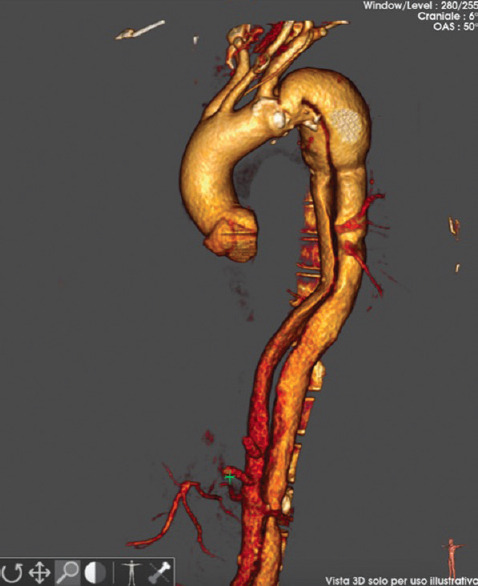

胸腔内血管主动脉修复术(TEVAR)在治疗急性和慢性主动脉病变方面发挥着核心作用。随着经导管结构性心脏手术的发展,超声心动图已成为手术指导的关键。尽管超声心动图在心脏介入手术中的应用已达成共识,但在主动脉手术中的超声辅助并没有广泛标准化。一名 71 岁的肥胖男子患有慢性 B 型主动脉夹层,在经食道超声引导下使用单支主动脉支架移植物(Endovastec™ Castor™)接受了 TEVAR 手术。术前评估确认降胸主动脉存在主动脉夹层,有一个后方真腔(TL)和一个前方假腔(FL),主动脉瓣解剖结构和功能正常,左心室功能正常,腔内无血栓,也没有妨碍支架移植物最佳植入的主动脉斑块。手术过程中,经食道超声心动图(TEE)监测导丝的定位、胸腔内支架导管的到达,然后将其植入主动脉弓和降主动脉。术后 TEE 评估强调支架移植物完全展开,无泄漏,并成功排除了开始形成血栓的 FL。血管造影证实动脉瘤已被排除,且无内漏。该临床病例展示了经食道超声心动图引导如何通过减少透视时间和造影剂的使用来改善 TEVAR 手术,并通过实时监测 TL 和 FL 来更好地评估夹层解剖结构。总之,经超声心动图可作为术中辅助成像工具,在术前、术中和术后提供良好的信息,提高 TEVAR 的成功率和安全性。

Thoracic endovascular aortic repair (TEVAR) plays a central role in managing acute and chronic aortic pathologies. With the advancement of transcatheter structural heart procedures, echocardiography has become a key in procedural guidance. Despite consensus on its use for cardiac interventions, ultrasound assistance in aortic procedures is not widely standardized. A 71-year-old obese man with chronic type B aortic dissection underwent a TEVAR procedure, using a single-branched aortic stent graft (Endovastec™ Castor™) and with transesophageal ultrasound guidance. The preprocedural assessment confirmed the presence of aortic dissection of the descending thoracic aorta with a posterior true lumen (TL) and an anterior false lumen (FL), normal aortic valve anatomy and function, normal left ventricular function, absence of intracavity thrombus, and absence of aortic plaques that could prevent the optimal implantation of the stent graft. During the procedure, a transesophageal echocardiogram (TEE) monitored the positioning of the guide wires, the arrival of the catheter of the thoracic endoprosthesis, and then the implantation of this at the level of the aortic arch and the descending thoracic aorta. Postprocedure TEE evaluation underlined full stent-graft deployment without leaks and successful exclusion of FL with the beginning of thrombosis. Angiography confirms the exclusion of the aneurysm and the absence of endoleaks. This clinical case demonstrates how transesophageal echocardiographic guidance can improve the TEVAR procedure by minimizing fluoroscopy time, contrast medium use, and enabling a better assessment of the dissection anatomy with real-time monitoring of both the TL and the FL. In conclusion, TEE can serve as an auxiliary intraoperative imaging tool to provide good information before, during, and after the procedure, increasing the success and safety of the TEVAR.